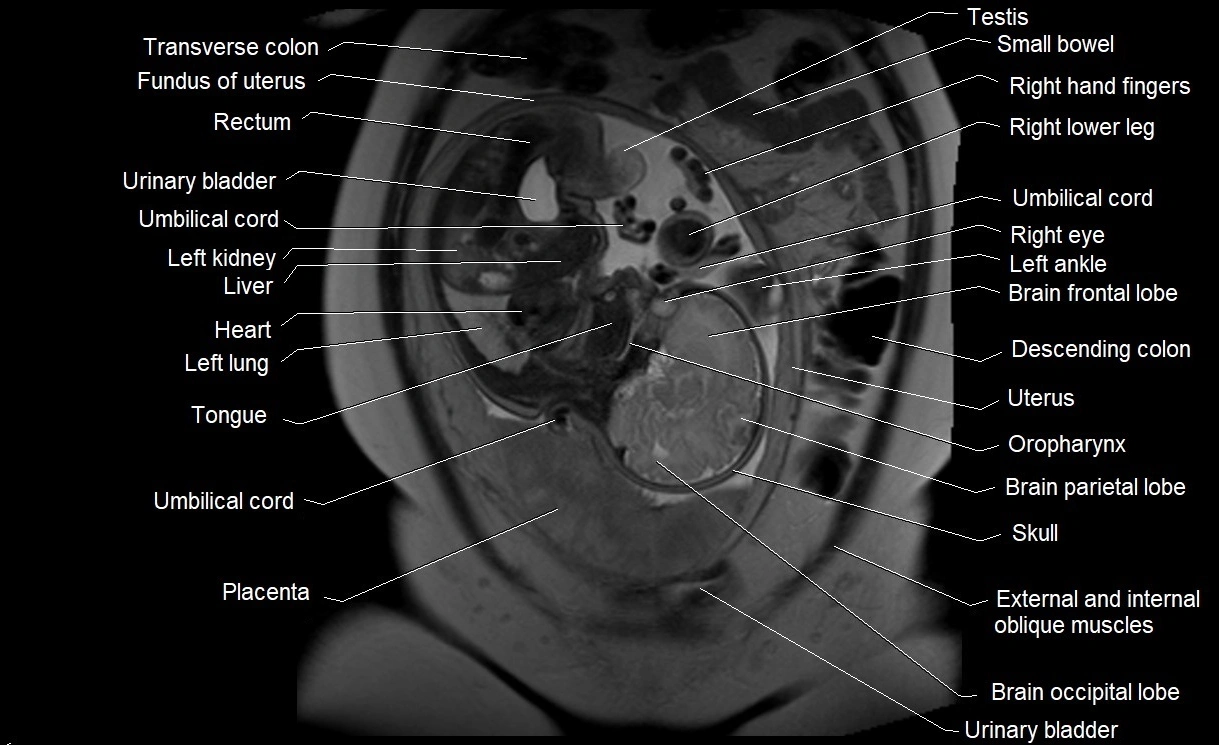

MRI Appearance

T2 HASTE (T2 GRE):

• Amniotic fluid shows very bright hyperintense signal

• Provides natural contrast against fetus and placenta

• Small particles (vernix) may appear as scattered hypointense foci within bright fluid

MRI image

image